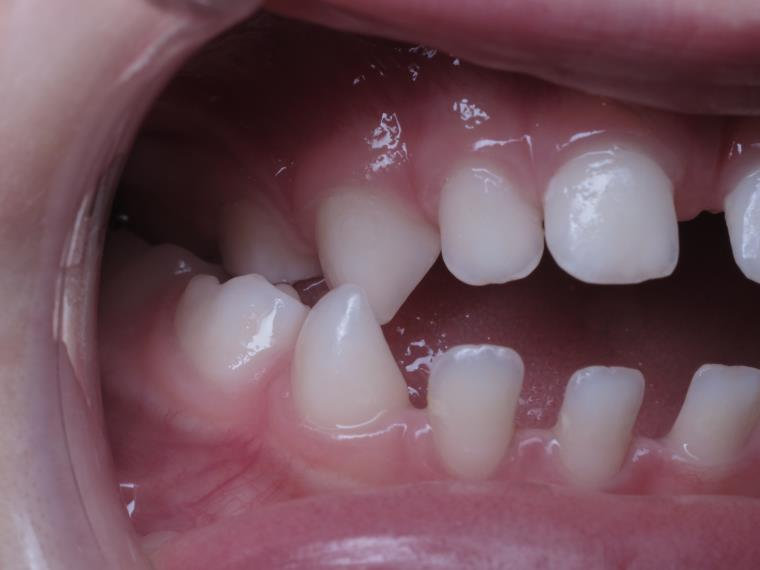

sectionnel multibagues pendant 8 mois

bilan de début et en cours de traitement